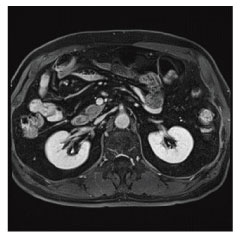

MRI(Magnetic Resonance Imaging:磁気共鳴画像診断装置)検査は、強力な磁石でできた円筒状の機械に入り、磁気や電波の力を利用して体の断面や血管を撮影する検査です。

当院のMRI画像集